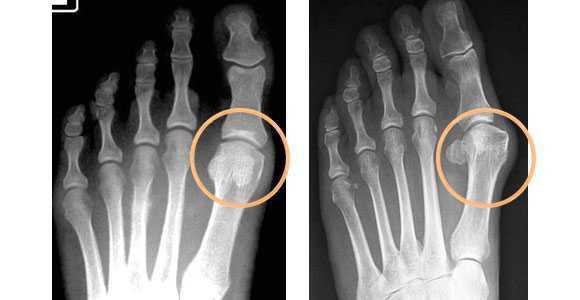

Степень плоскостопия по результатам рентгена:

- I степень — угол между 1-й и 2-й плюсневыми костями составляет 10-12°, а угол отклонения большого пальца 15-20°;

- II степень — углы увеличиваются до 15 и 30°;

- III степень — углы увеличиваются до 20 и 40°;

- IV степень — углы превышают 20 и 40° [17] .

Снимки в двух проекция выполняются поочерёдно для обоих ног. Степень поперечного плоскостопия определяют по углу отклонения 1-й плюсневой кости и большого пальца. На рентгенограммах проводят три прямые линии, соответствующие продольным осям 1-й и 2-й плюсневой кости и основной фаланге большого пальца [2] .